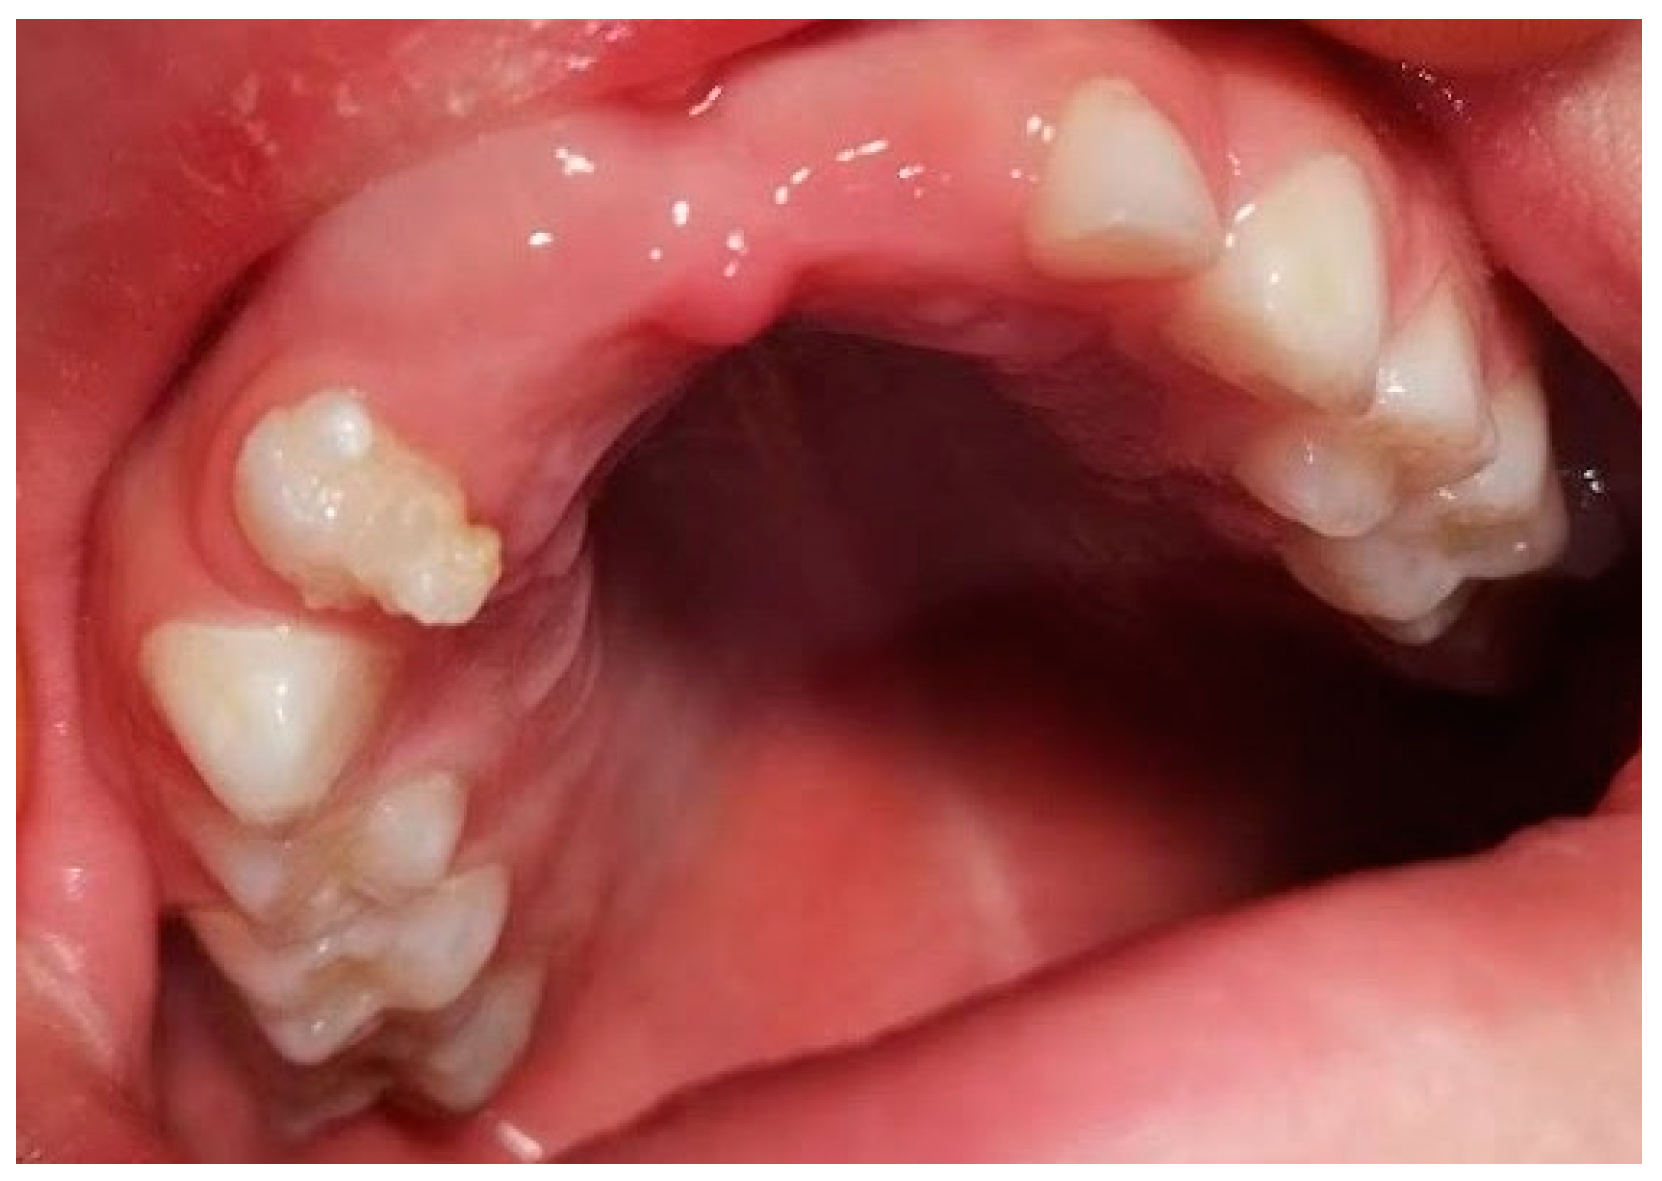

2. Case Presentation